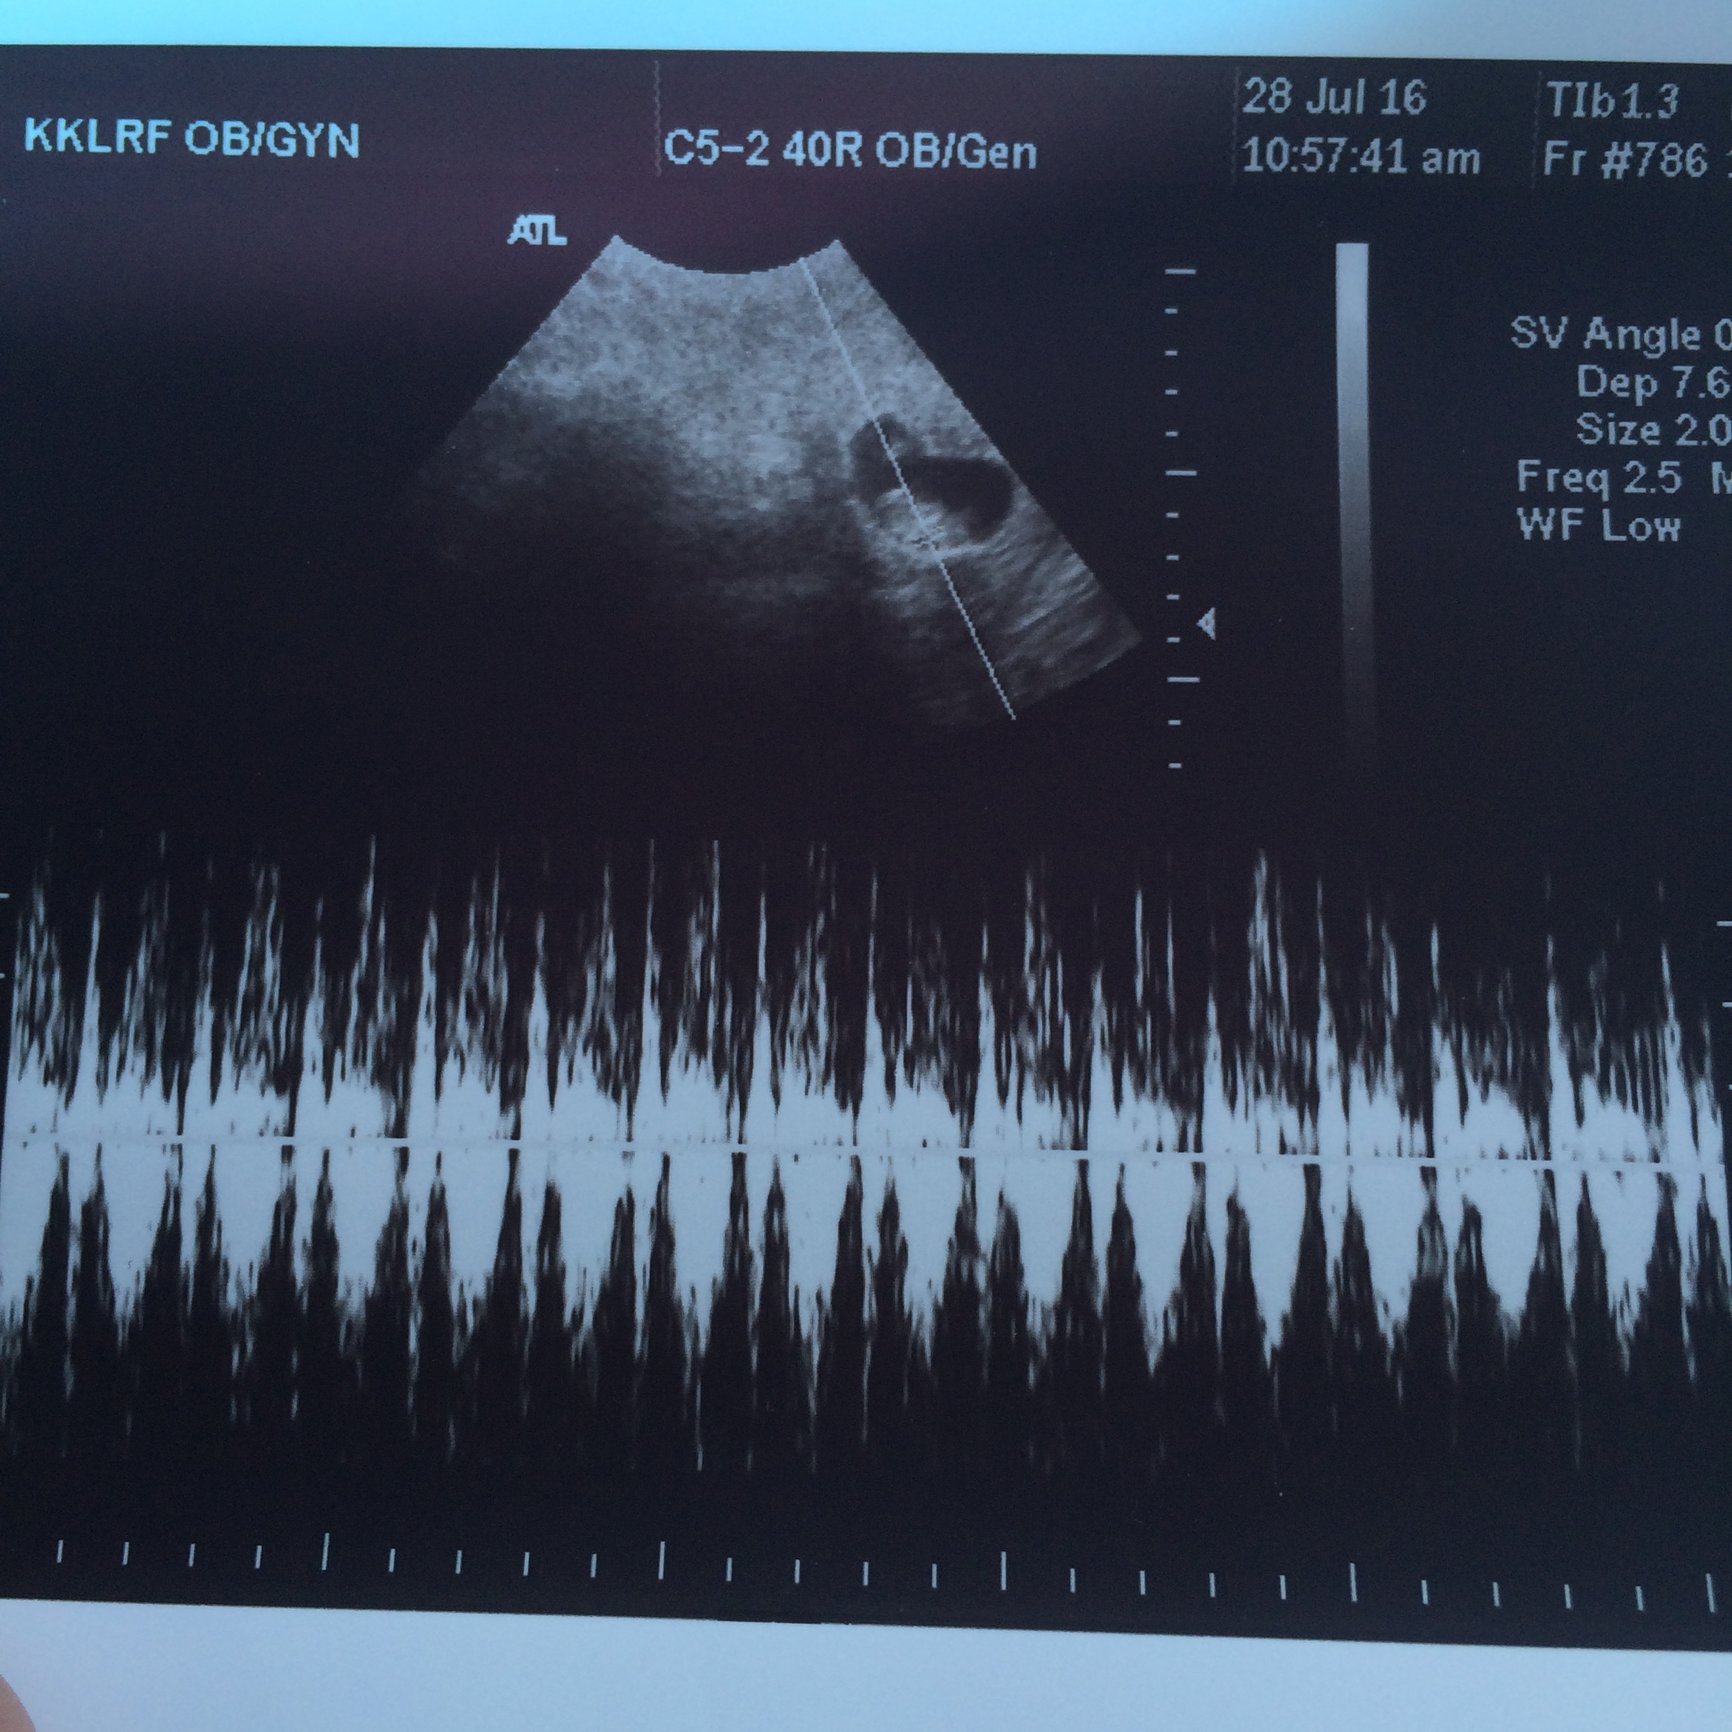

I still have the fear in the back of my mind (this ultrasound will be at 7w1d, and our first baby stopped growing at 7w1d), but I am still excited that things are looking good so far.

I got my test results today, my HCG level was 29,983. The doctor called me today to let me know that these results looked good and that my levels were progressing enough for her. Now I have my first ultrasound in 1 week! I'm so excited!